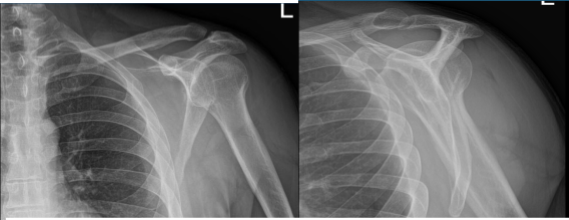

Right and Left shoulder X Ray were presented. On the right shoulder, there were no acute fractures however there is asymmetric widening of the acromioclavicular joint of the right shoulder and for further evaluation, correlation with MRI is recommended. On the other hand, the left shoulder X Ray showed normal radiographs.

Right Shoulder X-ray

Left Shoulder X-ray